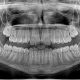

No lavarse los dientes tras la comida es la principal causa de caries. La manzana, puede, de forma esporádica, ser el sustituto del cepillo de dientes tras comer fuera de casa. Pero desde Clínica Dental Lucía Diéguez queremos insistir en que tomar manzana después de comer no es lo mismo que cepillarse los dientes.

Los dentistas recomiendan cepillar los dientes después de cada comida, pero el frenético ritmo de vida, las comidas fuera de casa e incluso la pereza hacen que más del 30% de los adultos españoles no se cepillen los dientes ni siquiera dos veces al día. Un mal ejemplo que cunde entre el 20% de los niños en ese país.

Un estudio publicado por la revista Britsh Dental Journal se suma a otras muchas investigaciones médicas previas para confirmar que morder una manzana fresca al finalizar una comida mejora la higiene bucal, ya que nos ayuda a generar saliva, reequilibrando el PH de la boca. En cada mordisco, su textura crujiente fricciona contra los dientes, limpiando los restos de alimentos que hayan podido quedar entre ellos. Y aporta azúcares naturales, que no pueden utilizar las bacterias para generar ácido, además de vitaminas que refuerzan las encías.